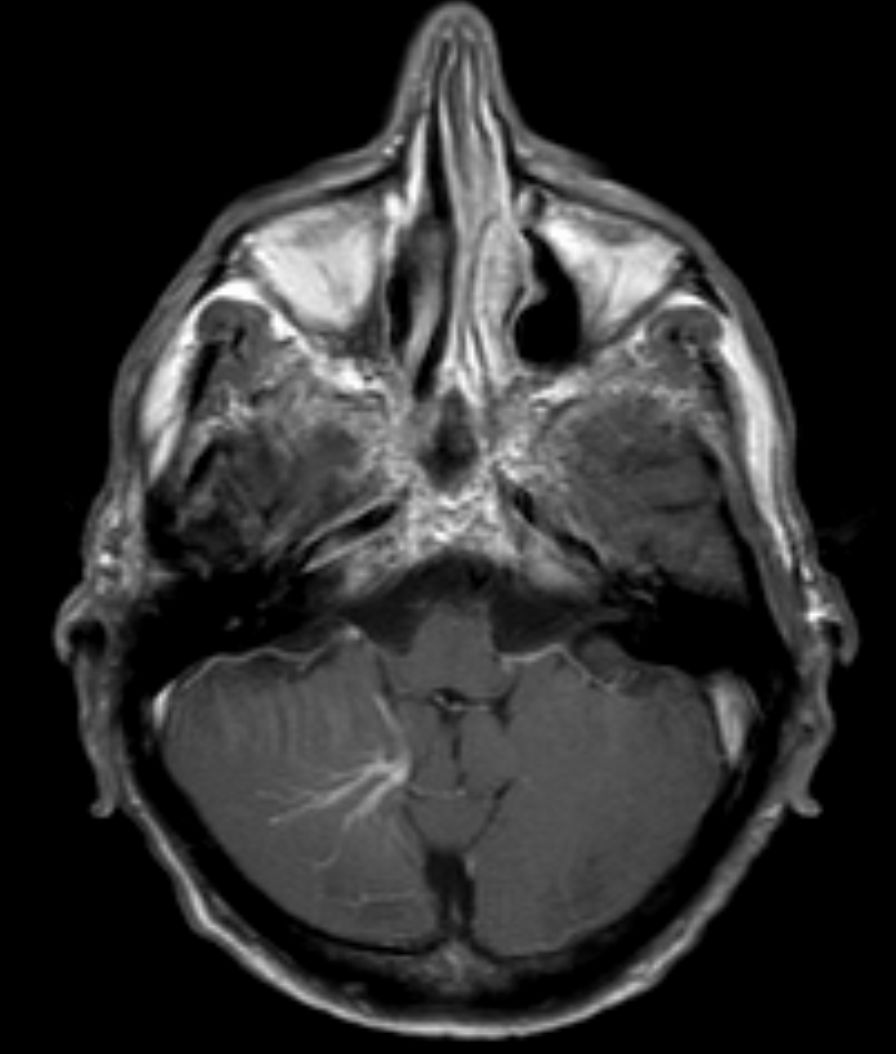

MSA

hot cross bun sign

hyperintensities of cerebellar peduncles